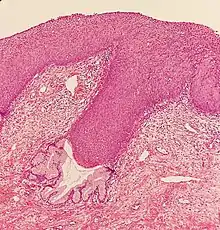

CIN is classified in grades:[14]

| Histology Grade | Corresponding Cytology | Description | Image |

|---|---|---|---|

| CIN 1 (Grade I) | Low-grade squamous intraepithelial lesion (LSIL) |

|

![]() |

| CIN 2/3 | High-grade squamous intraepithelial lesion (HSIL) |

| CIN 2 (Grade II) |

![]() | |

| CIN 3 (Grade III) |